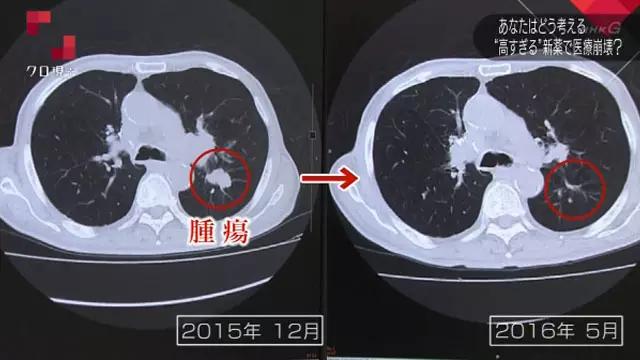

而且经过治疗,老人战胜了癌症的病魔,在影像里可以看到,肝脏里本来很大的一个“阴影”在经过了6个月的治疗后,几乎都快要不见了。伊坂光男每月花费800块钱,就基本治愈了肝癌!也就是总体花费才花了4800人民币!